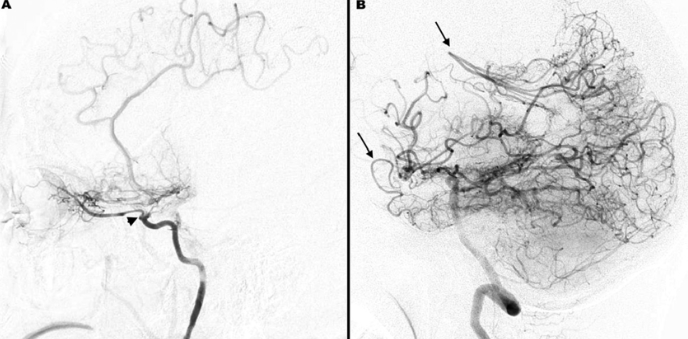

모야모야병은 뇌로 가는 혈관을 좁게 만들어 뇌세포가 필요한 산소를 공급받기 어렵게 만드는 질환입니다. 하지만 이런 일이 머릿속에서 일어나고 있는지 어떻게 알 수 있을까요?